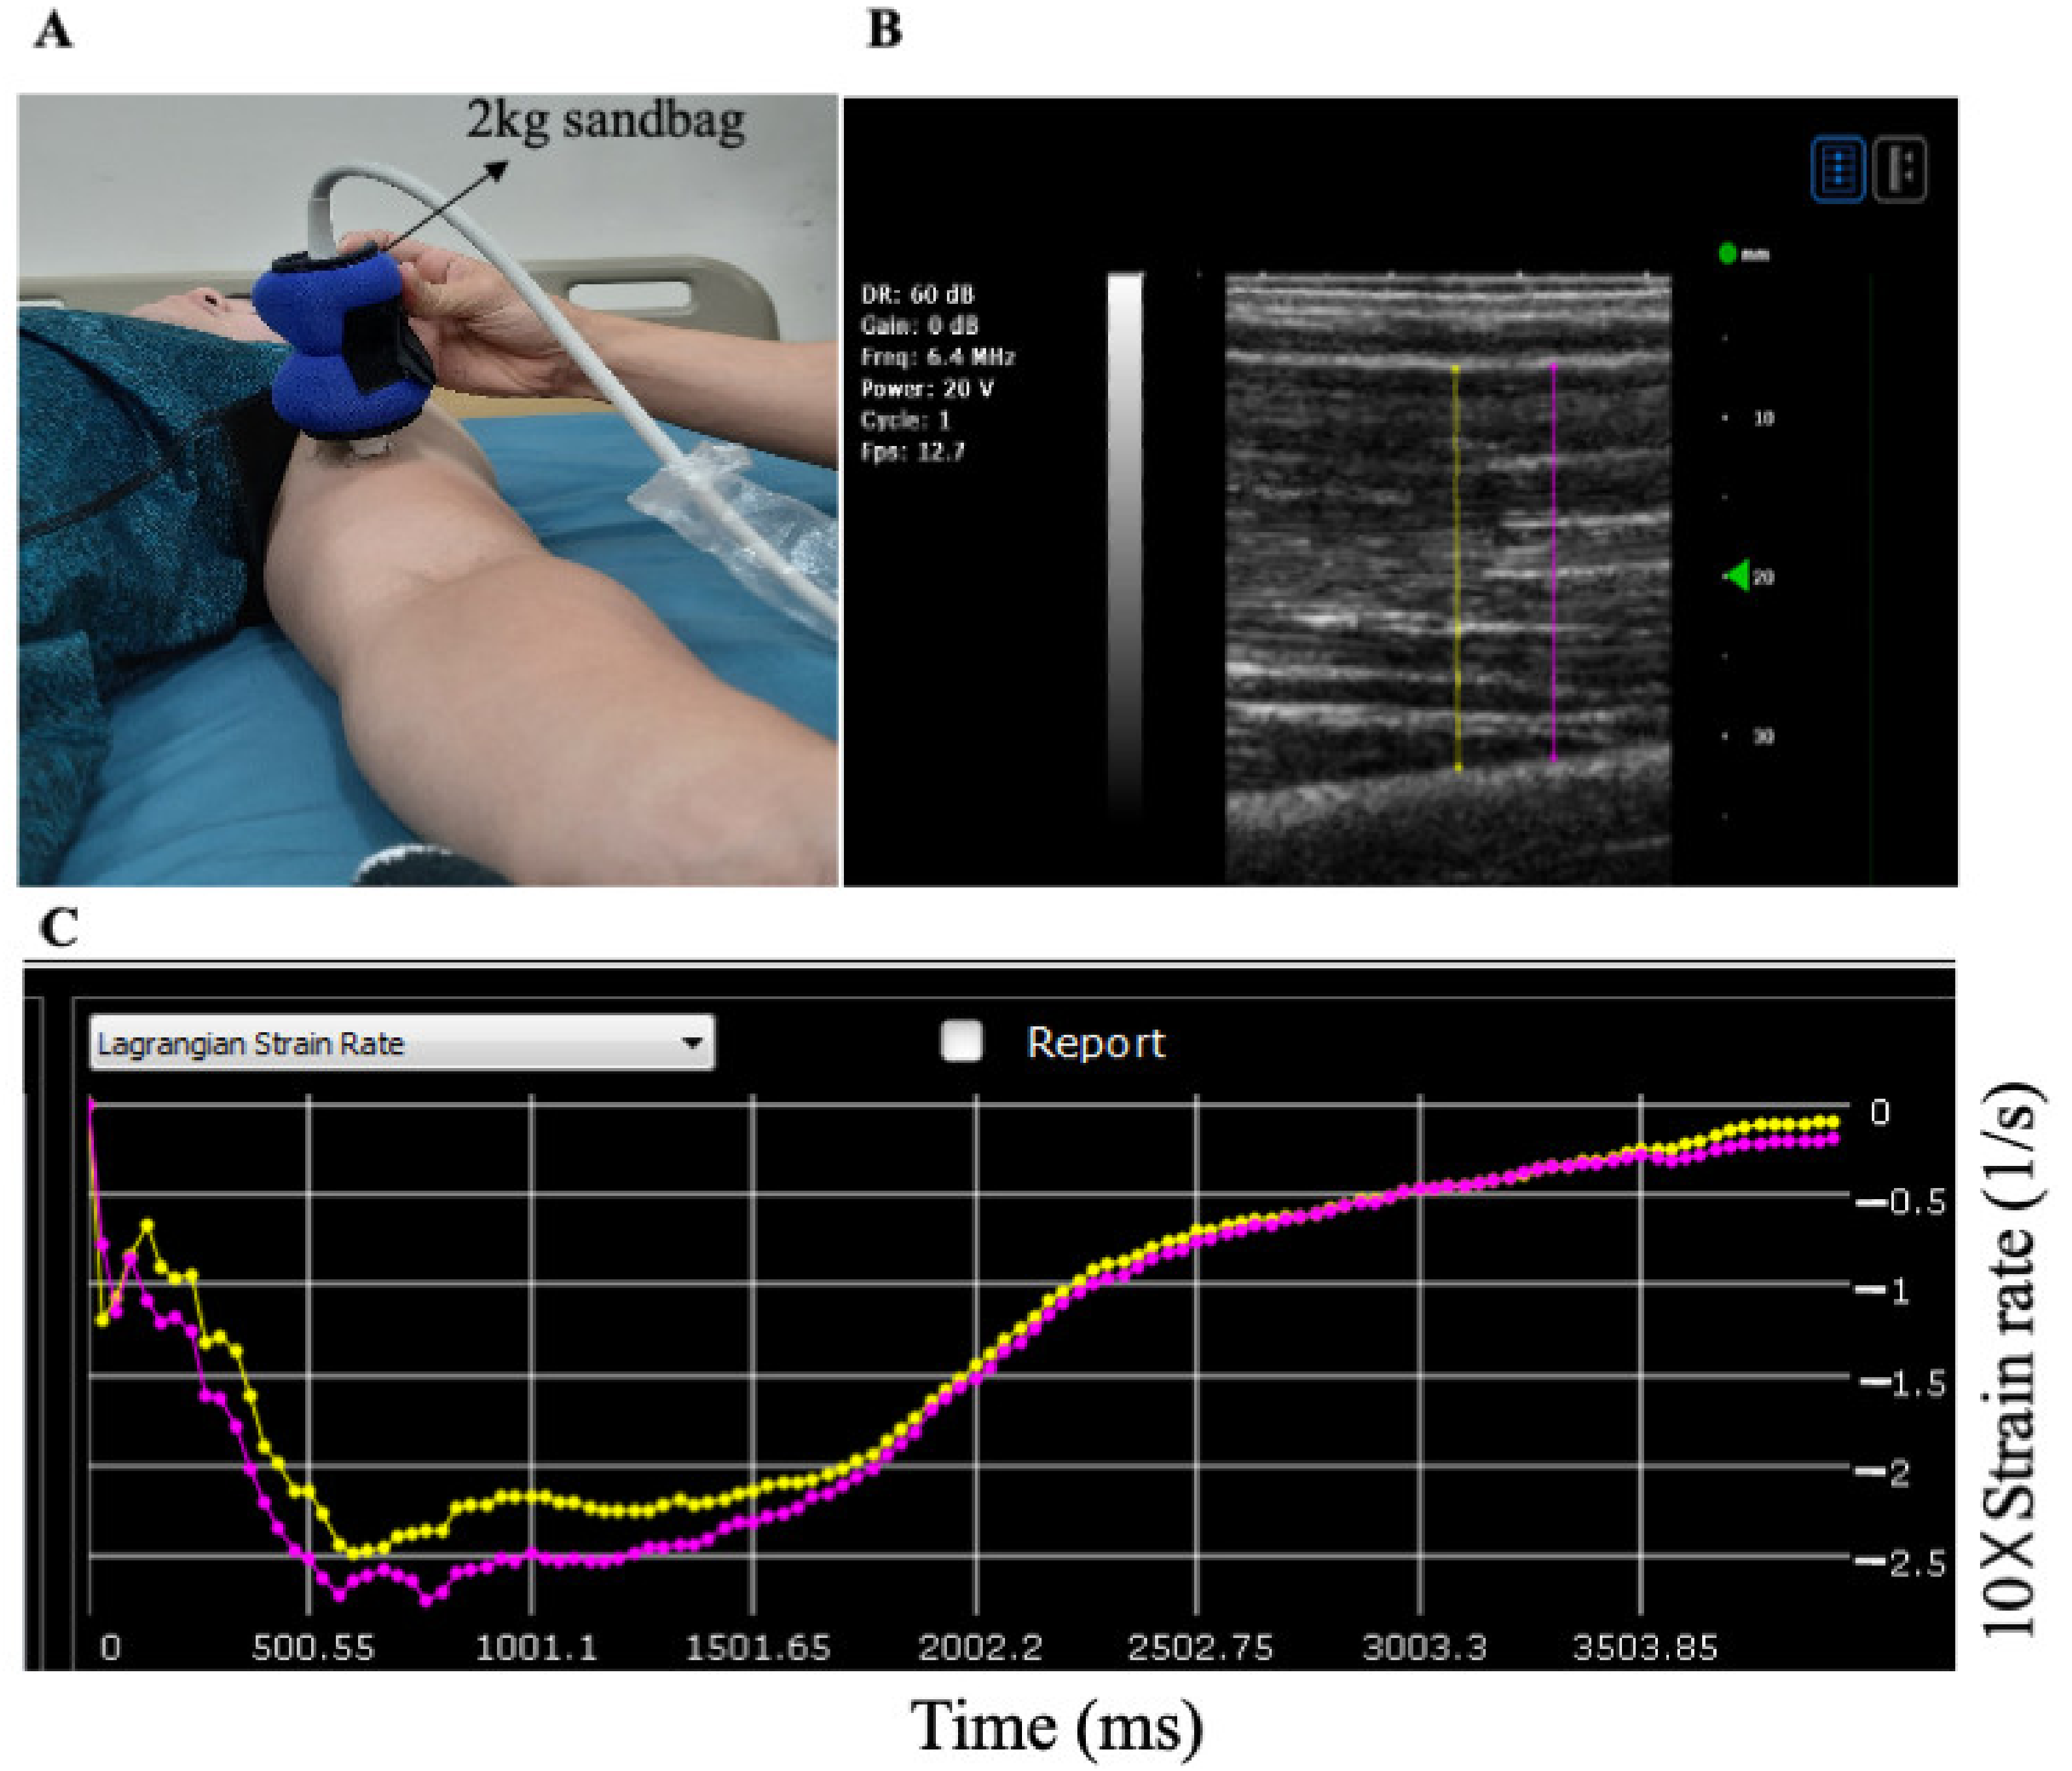

2.5. Muscle Stiffness

2.6. Arterial Stiffness